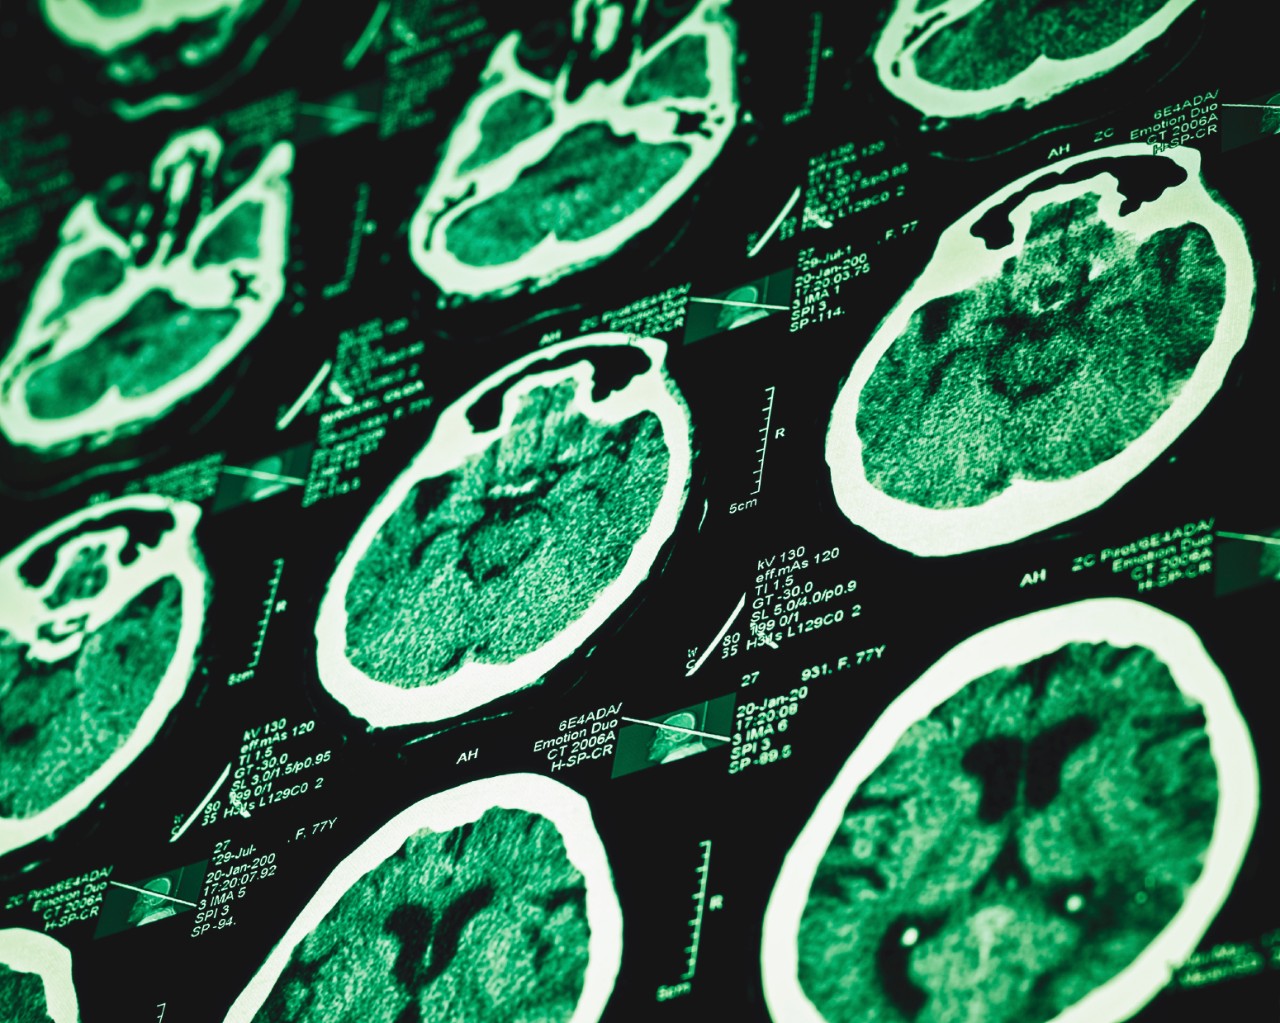

The prestigious journal The Lancet has published a large study identifying differences in the brains of people diagnosed with attention-deficit hyperactivity disorder (ADHD).

It found ADHD is associated with the delayed development of five brain regions, and should be considered a brain disorder. This is vindication for people experiencing ADHD whose diagnosis is sometimes called into question as an invented condition used to label normal children who are not meeting unrealistic expectations of “normal” behaviours.

Researchers from 23 centres in nine countries scanned the brains of people of aged four to 63 years, 1,713 with and 1,529 without ADHD. When they analysed all the data they found people with ADHD had slightly smaller brains overall, and in five of the seven specific regions there was a definite but very slight reduction in size.

They found these differences were more marked in children. When they analysed separately those who had and had not been treated with stimulant medication, they found no effect of medication. This suggests the differences are related to ADHD, and not an effect of treatment.